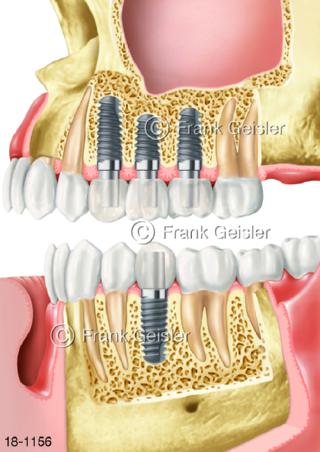

18-1156 Zahnimplantation Zahnimplantat Zahnwurzel

18-1157 Zahnimplantation Zahnimplantat Zahn